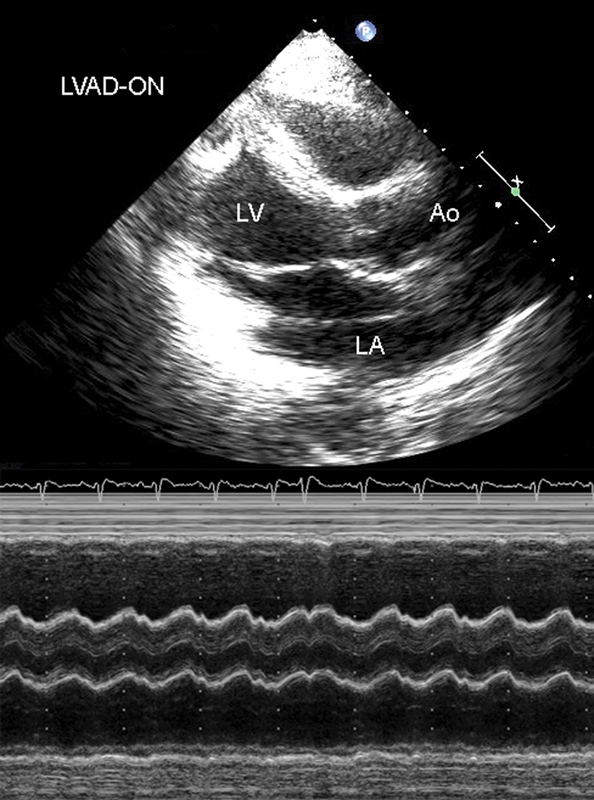

فحوصات تشخيصية لبعض امراض القلب والشرايين التاجية